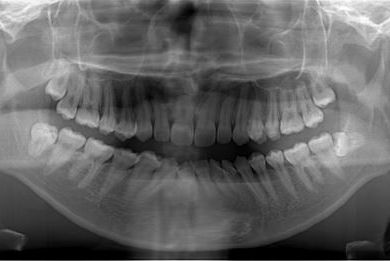

治療前

• 治療前